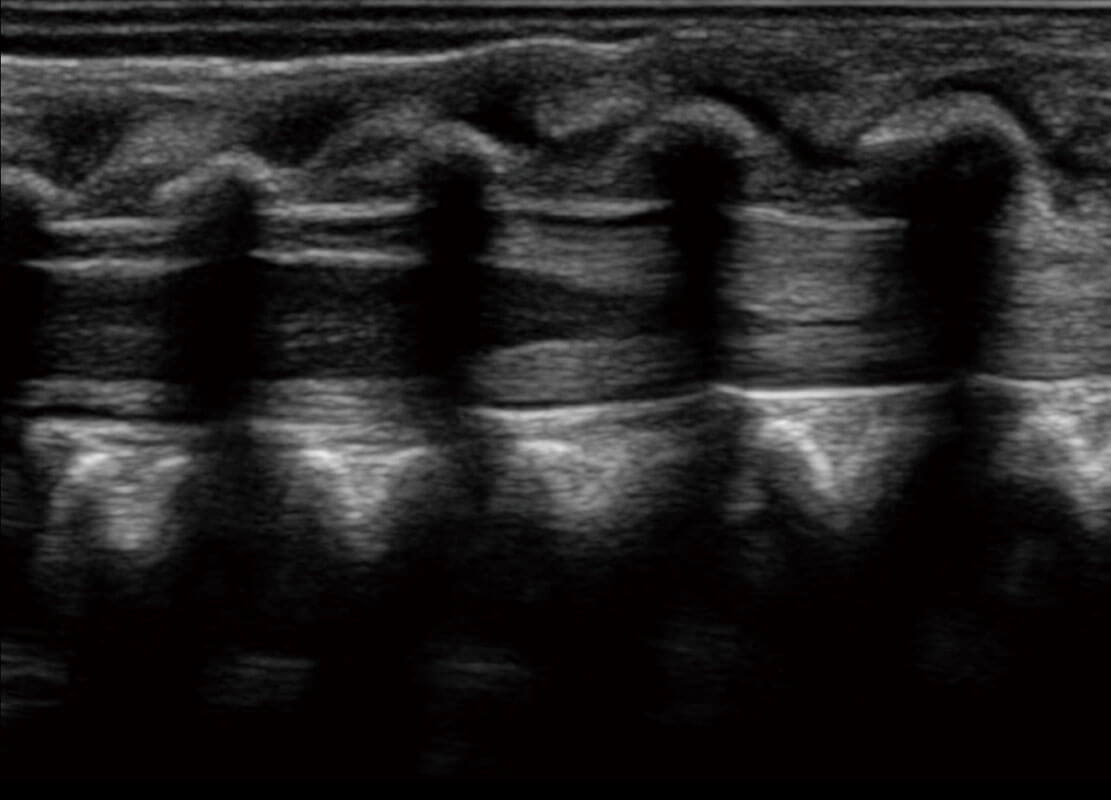

• 四腔切面

• 新生儿脊髓圆锥

• 新生儿心脏